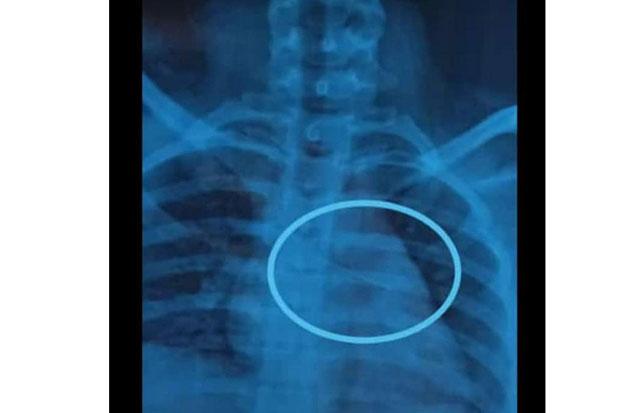

Hasil rongsen bocah perempuan yang menunjukkan posisi jarum pentul.(Foto : istimewa)

GUNUNGKIDUL, iNews.id-Dinda Nur Anggita, bocah asal Dusun Paliyan Kidul Kalurahan Karangduwet Kapanewon Paliyan, Gunungkidul harus menelan pil pahit. Di dalam dada sebelah kirinya bersarang sebuah jarum pentul.